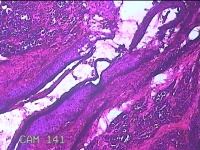

右侧头皮结节

性别

男

年龄

28岁

临床诊断

皮肤良性肿瘤

一般病史

发现右侧头皮结节3个月余,无明显疼痛及不适。

标本名称

大体所见

灰白暗红色组织1.5x1.2x0.8cm一块,表面带梭形皮肤1.5x1cm,皮下见结节1.5x1x0.3cm一个,结节表面有少许毛发,切开结节呈实性,切面灰白粉红色,质软。